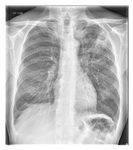

Radiografia de tórax mostrando pneumonia cavitando no lobo superior esquerdo

Da coleção do Dr. Jonathan Bennett. Usado com permissão